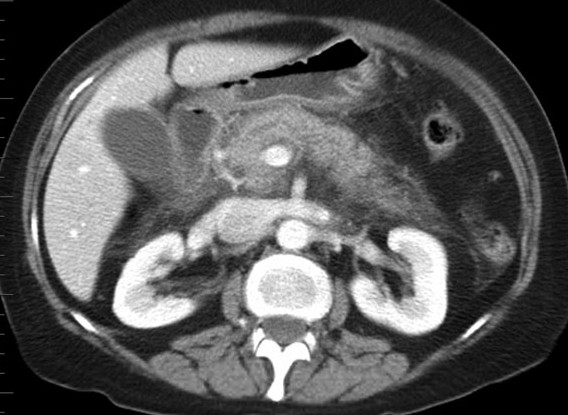

폭음을 가끔 하나 술과의 관련성이 불명확하여 복부 CT시행

췌장 주변의 지방 조직에 염증 파급 소견이 관찰되며 이외 해부학적 이상은 없음.